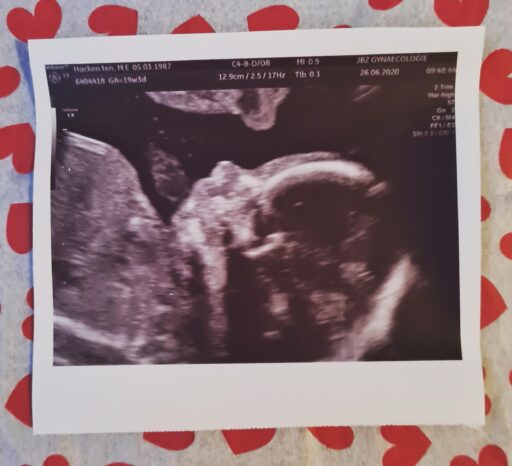

van baal is dat Daan niet mee mag naar controles in het ziekenhuis. De eerste echo waar hij bij mag

zijn is de 20 weken echo. Dat is wel jammer. Gelukkig is die nu alweer over twee weken. De tijd gaat

snel want dan ben ik alweer bijna op de helft!